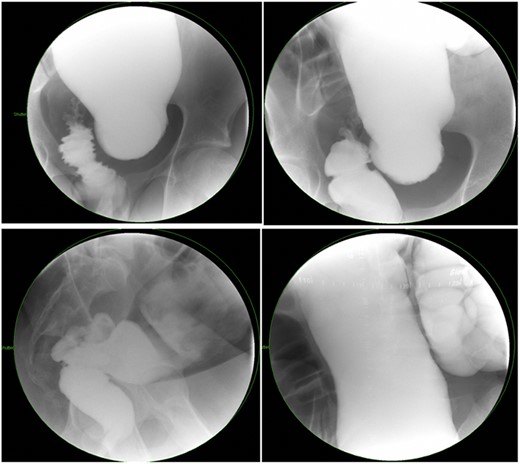

There is a subset of patients in whom primary transanal pull-through in those >2 years of age at the time of surgery is possible. While a previous case series reported that 18.8% of their late-diagnosed HD patients underwent transanal primary pull-through, these authors did not describe outcomes or reasons for choosing the operative approach [7]. In case series, the characteristics of patients who were able to undergo primary transanal-only pull-through include overall earlier age (2–6 years) vs. those diagnosed later. On contrast enema, they exhibited a limited degree of megacolon (Figs 1 and 2). Proximal colonic dilation was absent in all four patients that we felt were good candidates for a transanal-only approach. However, proximal colonic dilation (proximal of the sigmoid) was visualized in 15 patients, and therefore, a transanal-only approach was not offered. The ability to identify a clear transition zone low in the rectosigmoid was also observed in each patient. Finally, the ability to empty the colon preoperatively whether through laxatives or rectal irrigations was also present.

Representative contrast enema study. Note the lack of dilated proximal colon and defined transition zone in the low rectosigmoid colon. (Candidate for transanal only).

Representative contrast enema study of an older child with a large amount of proximal colonic dilation of the sigmoid and descending colon, seen here across multiple views during contrast enema (Not a candidate for transanal only).